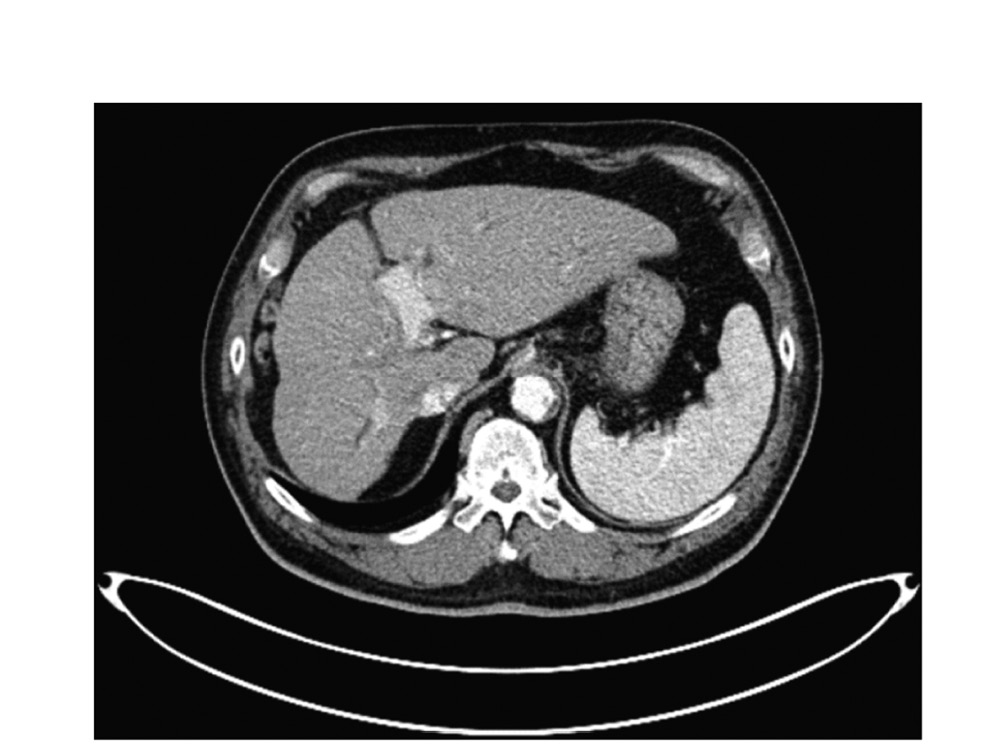

По данным спиральной компьютерной томографии (КТ) ОБП – в воротах печени определяются тканевые массы, распространяющиеся как вдоль протоков к желчному пузырю, так и в сторону печени (рис. 1).

Рис.1. Изображение компьютерной томографии – опухоль ворот печени.

Fig. 1. CT scan – hilar cholangiocarcinoma.